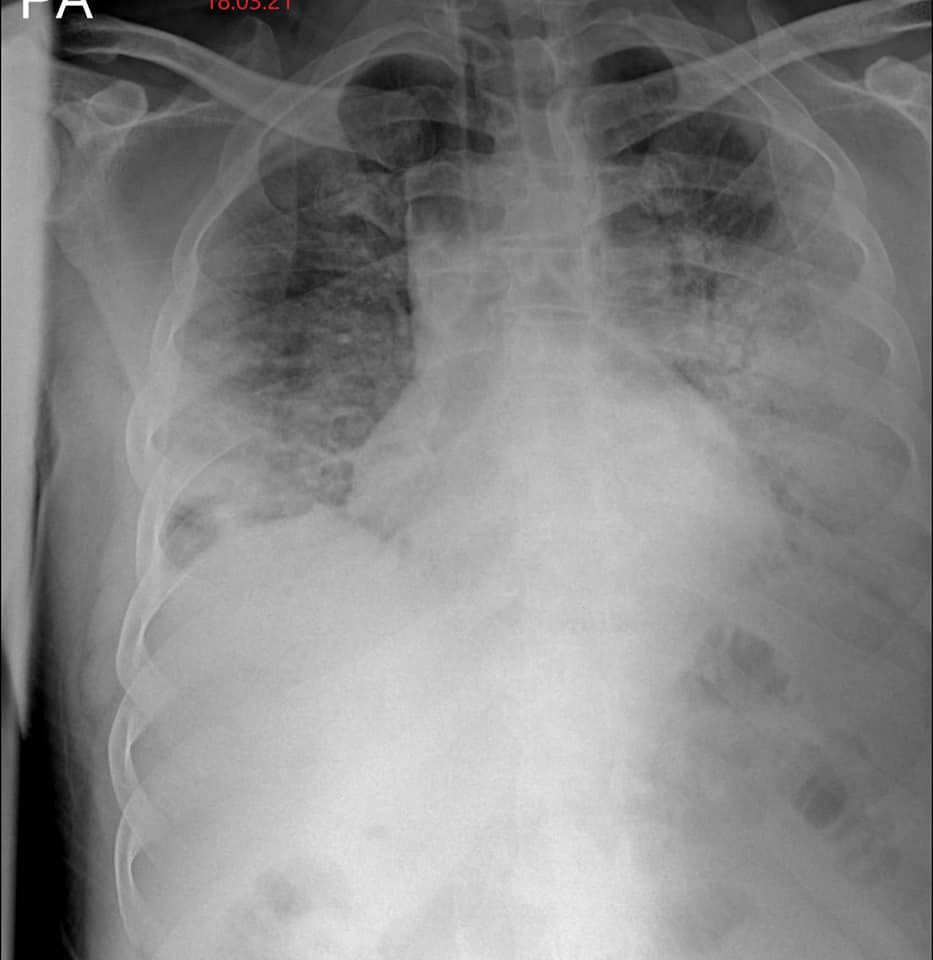

“មានបទពិសោធន៍ជាង1ឆ្នាំក្នុងគ្រប់គ្រង និងព្យាបាលជំងឺកូវីដដោយគ្មានការភ័យខ្លាចឬតក់ស្លុតឡើយ ។ តែក្នុង1ខែចុងក្រោយនេះចាប់ពី 20 កុម្ភៈ 2021 ខ្ញុំមានអារម្មណ៍ភ័យខ្លាច និងព្រួយបារម្ភណាស់ ពីព្រោះវាជាប្រភេទមេរោគប្រែរូបថ្មី (variant virus strain) ដែលក្នុងរយៈពេលតែ2ទៅ5ថ្ងៃវាវាយលុកចូលសួតធ្វើអោយរលាកធ្ងន់ធ្ងរទាំងសងខាង ។ រូបភាពសួតត្រូវបានមេរោគស៊ីសុះសាច់ដ៏គួអោយខ្លាច ។